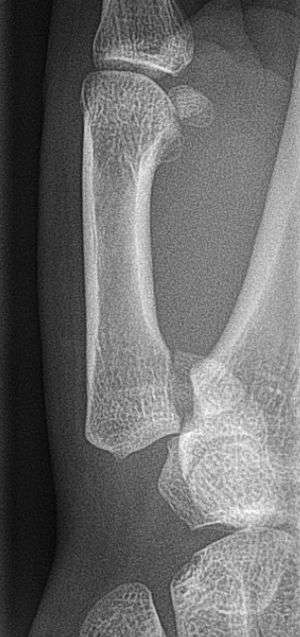

Bennett fracture on x-ray | |

Bennett fracture is a fracture of the base of the first metacarpal bone which extends into the carpometacarpal (CMC) joint.[1] This intra-articular fracture is the most common type of fracture of the thumb, and is nearly always accompanied by some degree of subluxation or frank dislocation of the carpometacarpal joint.

In the case of the Bennett fracture, the proximal metacarpal fragment remains attached to the anterior oblique ligament, which in turn is attached to the tubercle of the trapezium bone of the CMC joint. This ligamentous attachment ensures that the proximal fragment remains in its correct anatomical position.

The distal fragment of the first metacarpal bone possesses the majority of the articular surface of the first CMC joint. Unlike the proximal fracture fragment, strong ligaments and muscle tendons of the hand tend to pull this fragment out of its correct anatomical position.